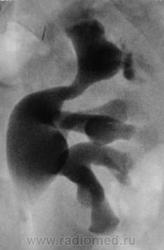

Гидронефротическая трансформация слева вследствие блока, вероятно, частичного, конкрементом в в/3 мочеточника (ПУС).

крррасиво, но сначала запереживал за правую..интересный вариант строения ЧЛС слева, почти неполное удвоение?

Порой, на фоне такой подготовки, сложно разобраться есть оно удвоение, или нет его.